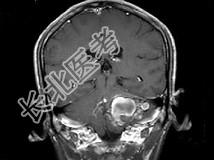

- 单项选择题男,45岁, 反复呕吐近1个月,加重5天, 根据所提供图像,最可能的诊断是 ( )

A、海绵状血管瘤

B、静脉血管畸形

C、脑出血

D、动静脉畸形

E、小脑胶质瘤并出血